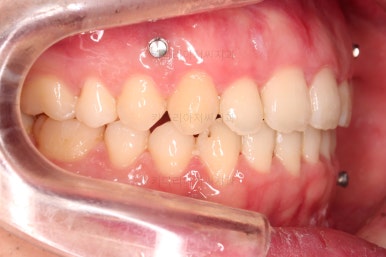

수술 전 교정과정이 거의 마무리 되어 갑니다.

오히려 앞니가 거꾸로 물리는 정도는 더 심해지고요.

수술 직전이 얼굴모습도 가장 주걱턱이 심한 양상으로 됩니다.

농담 삼아 못생겨지면 못생겨질수록 수술이 더 잘될겁니다 라고 말씀 드립니다.